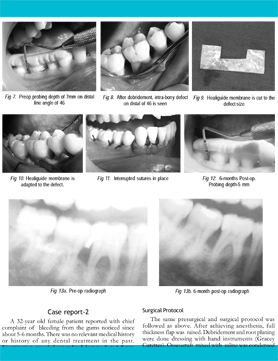

OSSEOGRAFT ® (DMBM - Xenograft)

&HEALIGUIDE ® (Bioresorbable GTR/GBR Membrane)

Treatment of peri-endo Lesion (2015)